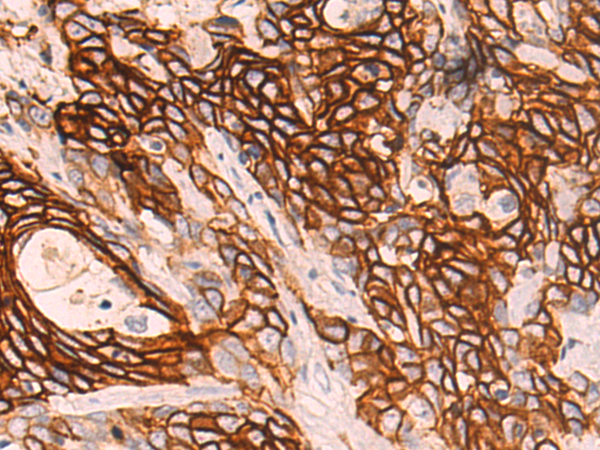

分类: 科研抗体货号: P10703别名: ARO; ARO1; CPV1; CYAR; CYP19; CYPXIX; P-450AROM应用: IHC反应种属: Human, Mouse, Rat